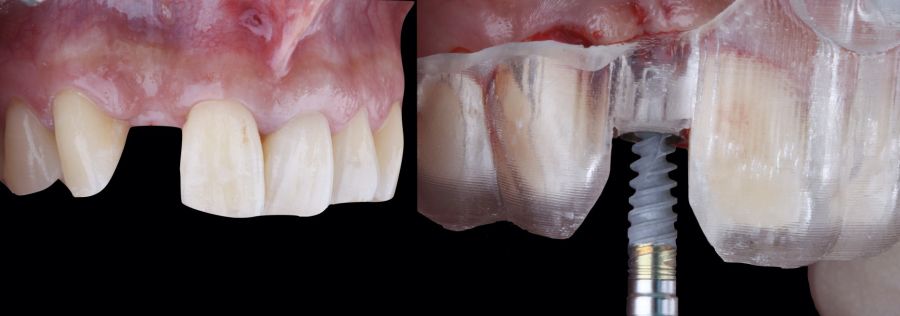

-Fase I: se realizó la extracción atraumática del resto radicular 1.2 y se efectuó un legrado del tejido de granulación. A continuación, se realizó el relleno del alveolo mediante un injerto óseo bovino inorgánico (0,25-1mm) combinado con fibrina autóloga rica en plaquetas y leucocitos. Finalmente, se suturó aproximando los bordes mediante 4 puntos simples desde el margen mucoso vestibular al palatino. Después, la paciente siguió usando su prótesis parcial removible como restauración provisional (Figura 1).

-Fase II: la cicatrización transcurrió sin complicaciones. Tras 5 meses de la cirugía de preservación alveolar, se planificó la cirugía implantológica guiada en posición 1.2 (Figura 2). Para ello, se utilizaron un archivo DICOM procedente de la tomografía computarizada de haz cónico (CBCT) y el archivo STL procedente del escaneado mediante un escáner óptico intraoral. Con esta información se construyó una férula quirúrgica de soporte dental (Figura 3). La férula quirúrgica se ancló sobre los dientes y guió la realización del lecho implantario y la colocación del implante. La técnica quirúrgica de cirugía guiada consistió en una cirugía con colgajo, preparando e insertando el implante (3,5 x 11,5 mm) según el protocolo estandarizado de cirugía guiada Nobel Active® (Nobel Biocare AB, Gothenburg, Sweden). Una vez colocado el implante 1.2, se obtuvo un injerto gingival compuesto de epitelio y tejido conectivo de la mucosa masticatoria palatina. A continuación, se realizó la desepitelización de la capa superficial de dicho injerto fuera de boca mediante una hoja de bisturí 15C con la finalidad de obtener un injerto de tejido conectivo de la capa subyacente18.

El injerto desepitelizado se insertó y posicionó por vestibular y oclusal mediante un punto colchonero horizontales utilizando sutura 5-0 no reabsorbible (Figura 4)19.